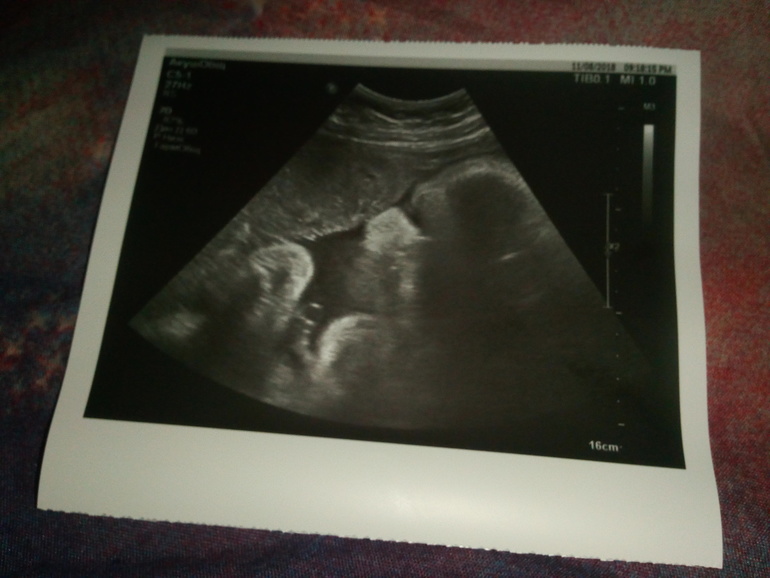

И так ... 9.11 на сроке 38 недель сходила я на УЗИ. Всё хорошо! Слава Богу ни каких патологий, обвитий и т.д. Малявочка моя уже весила 3кг 662гр.

Всю ночь просыпалась от переживаний. Когда заходила в кабинет начало меня подтряхивать. Но оказалось что напрасно. Моя малявочке в порядке. Ни каких обвитий и отклонений. Воды в норме. Вес уже 2096 гр. (совсем не маленькая малявочке😀). Окружность головы...